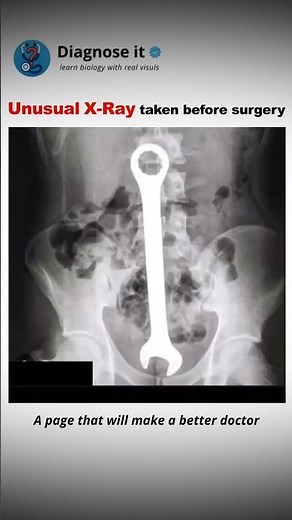

Unusual X-Ray #biology #doctor #explore #health #mbbs #medical

Diagnose it

X-rays reveal painful household objects in an unlikely place

These x-rays are both funny and make me feel very sorry for the people in these painful and embarrassing situations.